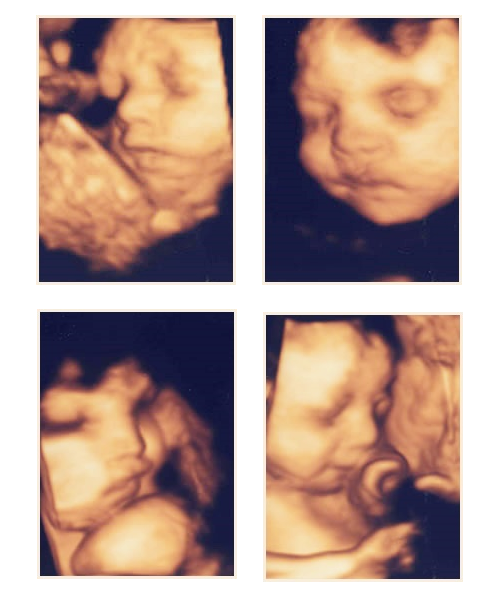

■実際の4D超音波画像

顔の上部にある程度羊水スペースがあり、手足などで覆われていなければ写真のように胎児の表情や動きをリアルタイムに観察できます。

以下の写真は当院で妊婦検診を受けられている患者様の赤ちゃんです。

■なぜ4D超音波の画像は金色なんですか?

画像の色彩は選択できるようになっています。金色は見た目に美しく、また立体的に描写するのに必要な影やハイライトをきれいに表示できるので、多くの先生方が使われています。